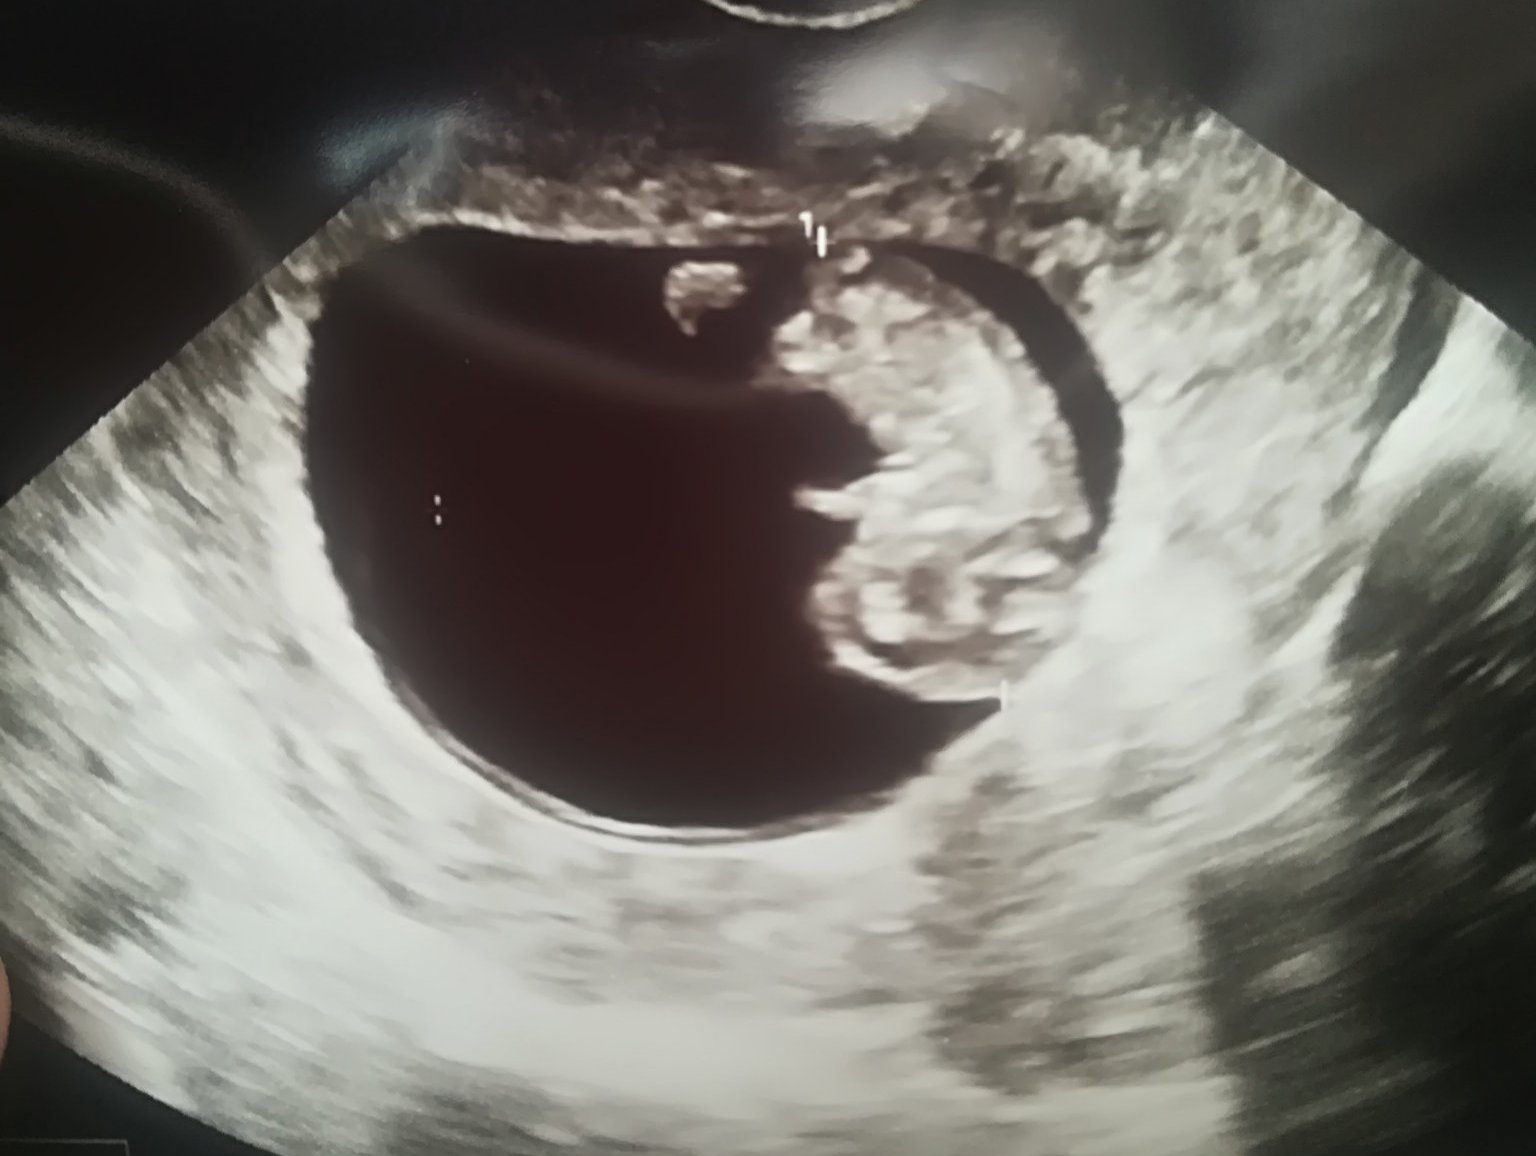

Кога се прави ранната фетална морфология?

Кога трябва да е следващият преглед след 6 седмици и 4 дни?